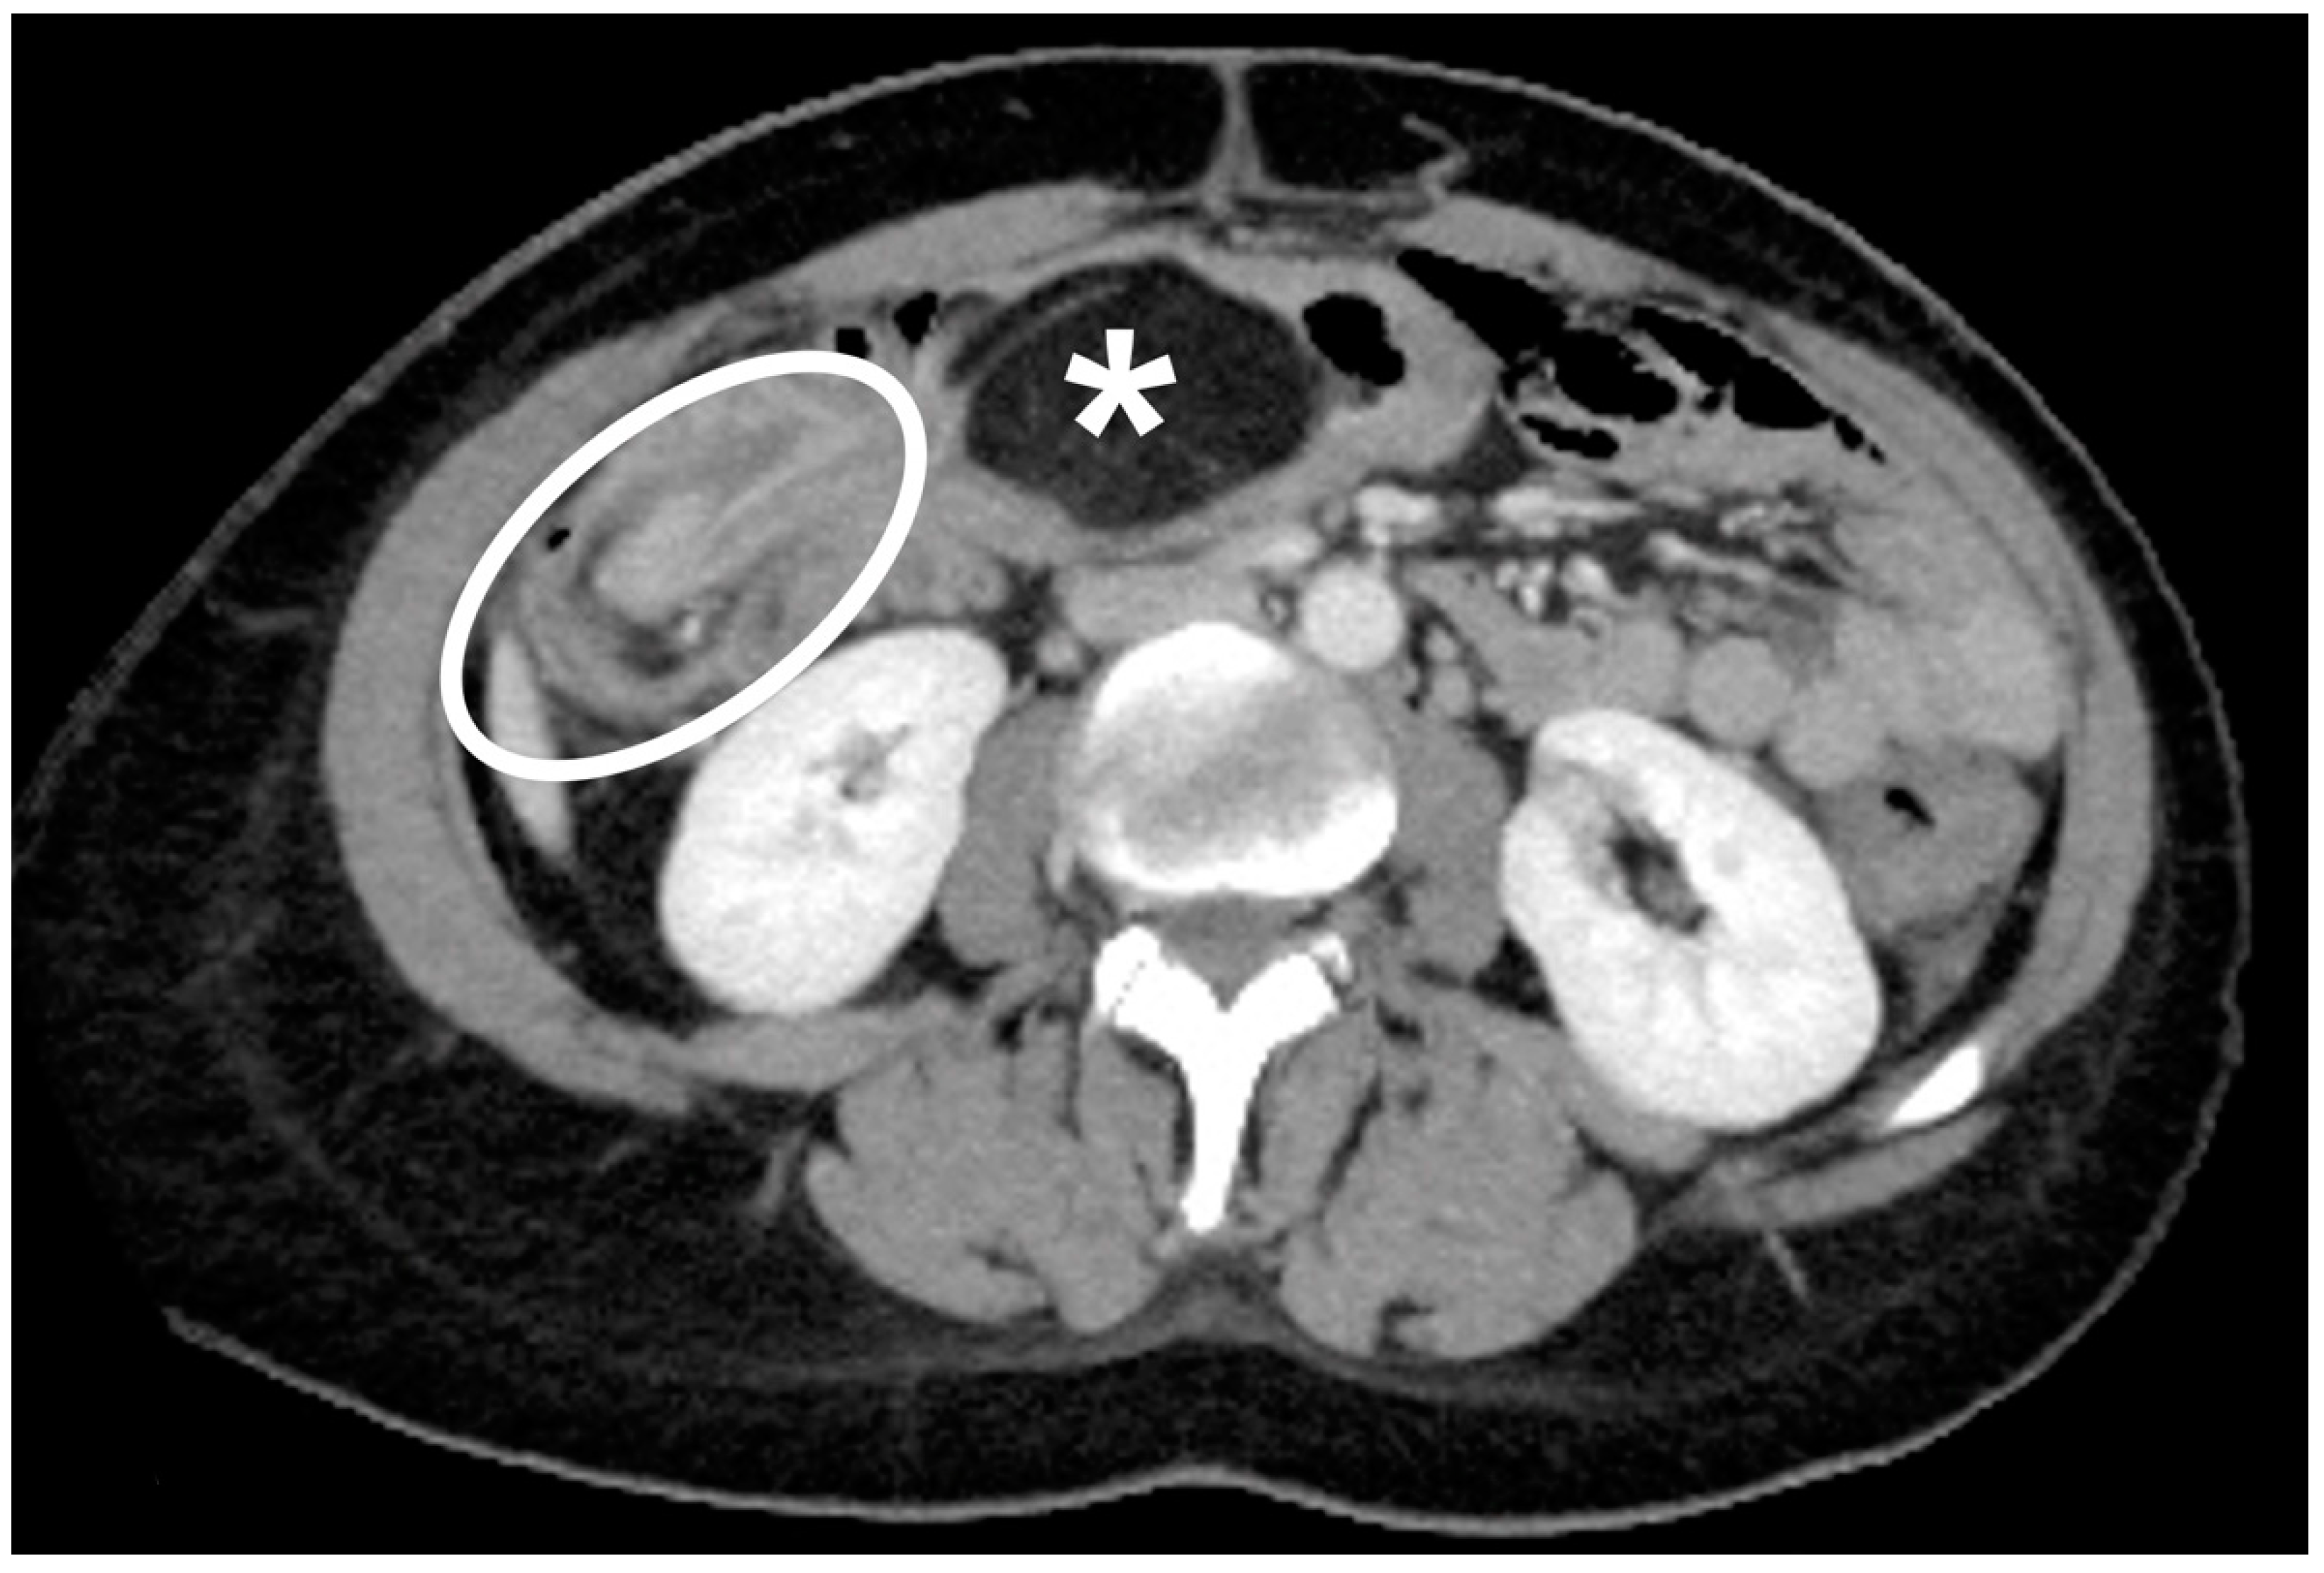

2. Materials and Methods

3.3. Instrumental Examinations